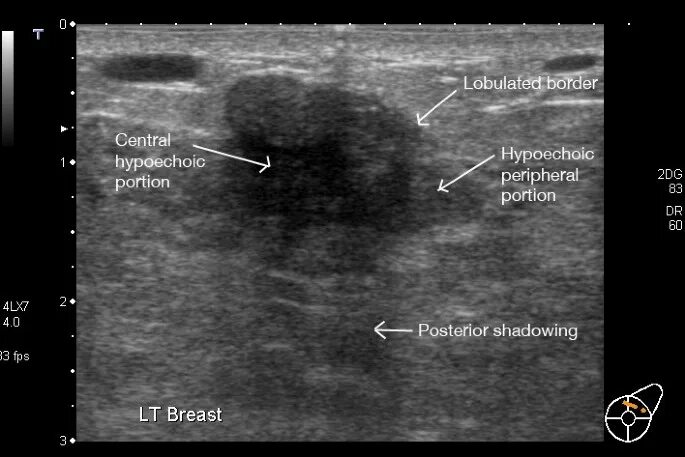

Как выглядит фиброаденома молочной железы